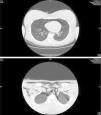

Chest CT scan showed a large pneumomediastinum with bilateral pneumothorax (Figure 1).

Figure 1. Chest CT showing a large pneumomediastinum associated with a minimum layer of bilateral pneumothorax, more visible on the left (maximum thickness 17 mm) associated with huge subcutaneous emphysema in the sovraclavear region, in the neck and in the laterocervical bands bilaterally.